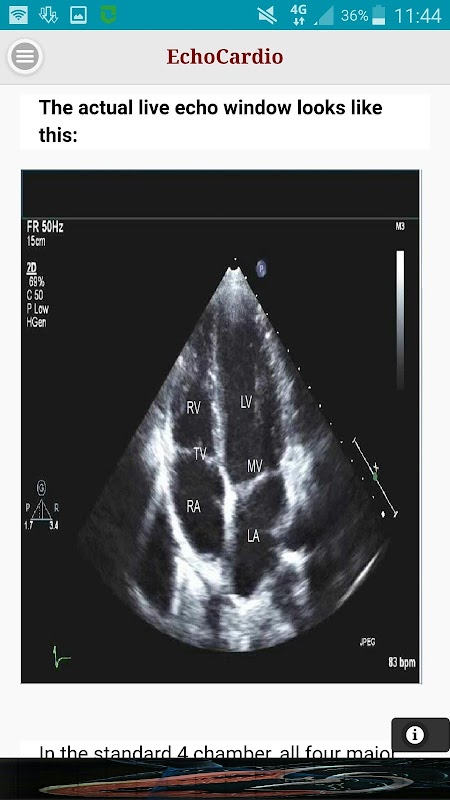

apikal